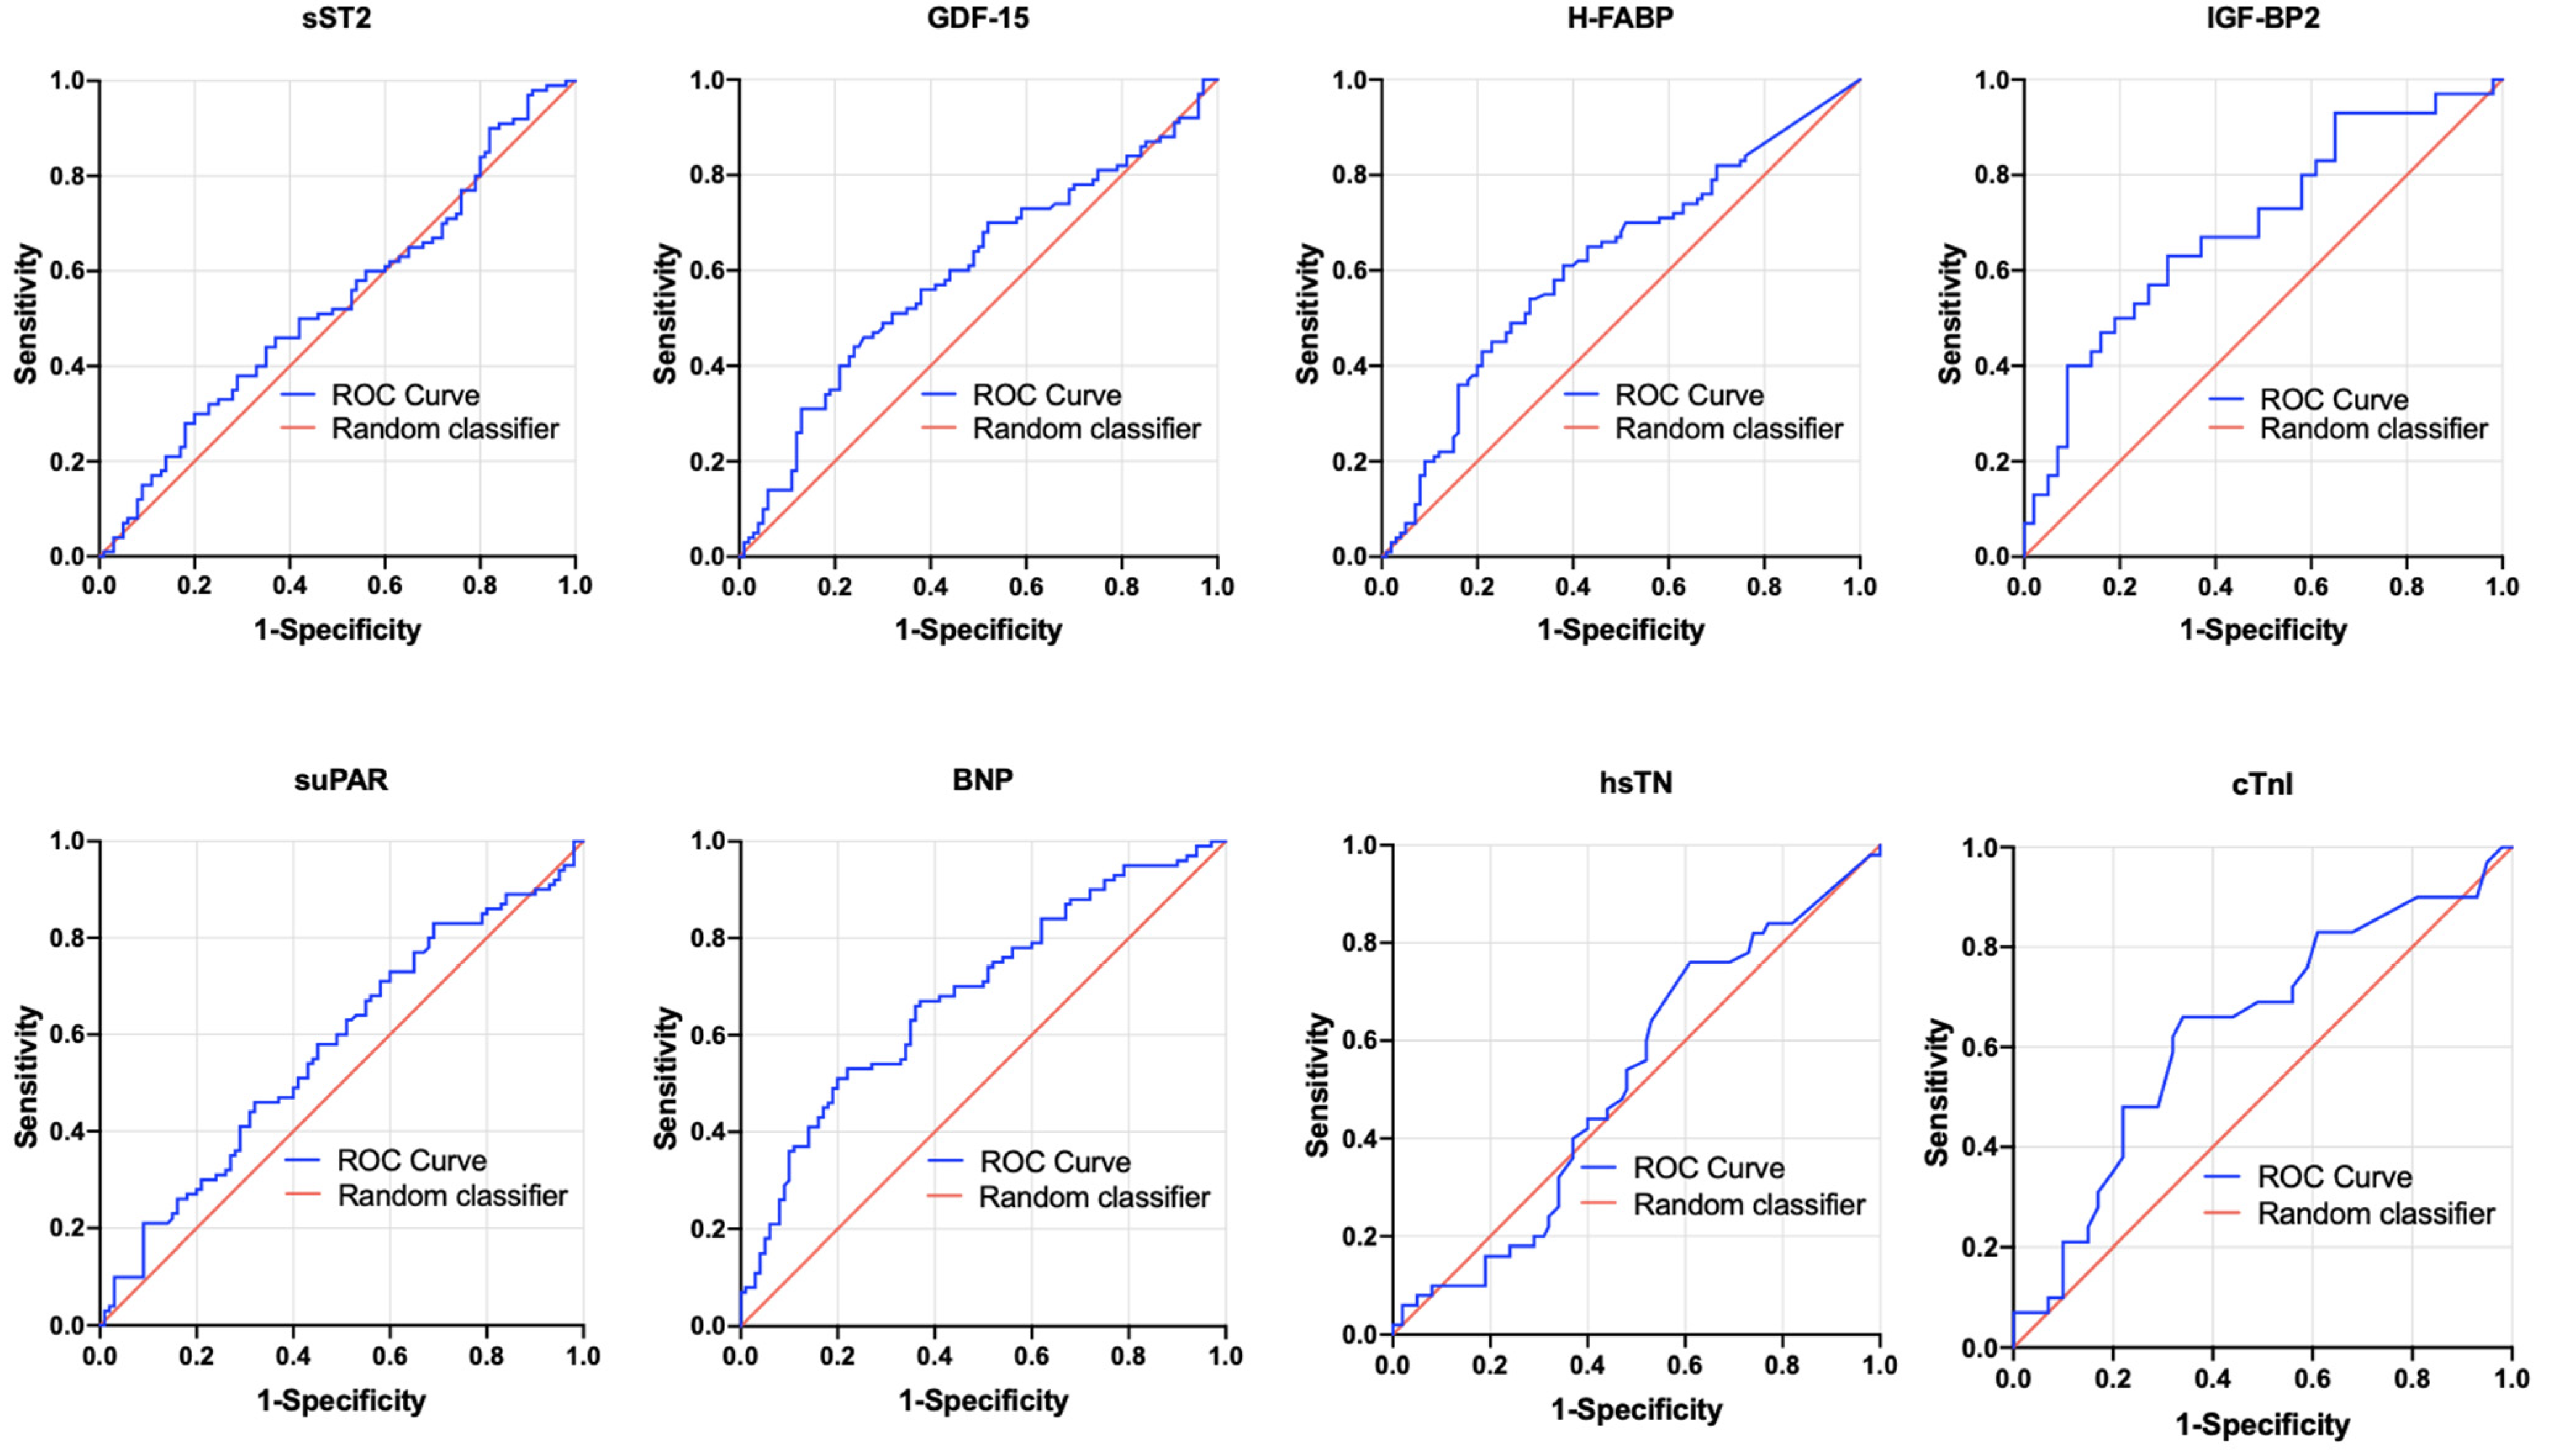

3.6. AUROC Results—PA/BSA vs. Singular Biomarkers

3.7. AUROC Results—PA/BSA vs. Dual-Biomarker Combinations

| sST2 (pg/mL) | PA/BSA ≥ 16.6 mm/m2 | 0.466 | 0.382–0.550 | 0.433 | 11,545.5 | 0.72 | 0.33 | 0.05 |

| GDF-15 (pg/mL) | PA/BSA ≥ 16.6 mm/m2 | 0.595 | 0.509–0.680 | 0.029 | 1172.0 | 0.44 | 0.76 | 0.20 |

| H-FABP (ng/mL) | PA/BSA ≥ 16.6 mm/m2 | 0.616 | 0.533–0.700 | 0.080 | 1.6 | 0.54 | 0.69 | 0.23 |

| IGF-BP2 (pg/mL) | PA/BSA ≥ 16.6 mm/m2 | 0.694 | 0.570–0.818 | 0.050 | 198,440.4 | 0.63 | 0.70 | 0.33 |

| suPAR (pg/mL) | PA/BSA ≥ 16.6 mm/m2 | 0.572 | 0.487–0.656 | 0.097 | 2753.9 | 0.83 | 0.31 | 0.14 |

| BNP (pg/mL) | PA/BSA ≥ 16.6 mm/m2 | 0.684 | 0.604–0.764 | <0.001 | 2194.0 | 0.51 | 0.80 | 0.32 |

| hsTN (pg/mL) | PA/BSA ≥ 16.6 mm/m2 | 0.518 | 0.410–0.626 | 0.748 | 2.0 | 0.76 | 0.39 | 0.15 |

| cTNI (pg/mL) | PA/BSA ≥ 16.6 mm/m2 | 0.635 | 0.501–0.770 | 0.055 | 24.5 | 0.66 | 0.66 | 0.31 |